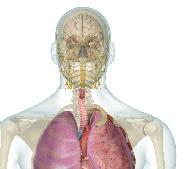

Orgány a tkáně, které tvoří naše tělo, jsou uspořádány do skupin, které lékaři nazývají soustavy. Každá soustava vykonává určitou práci. Například trávicí soustava rozkládá potravu na živiny, které tělo dokáže absorbovat. Oběhová soustava dopravuje tyto živiny a další důležité chemické látky do celého těla. Některé z důležitých tělních soustav jsou uvedeny níže.

Nervová soustava

Tato soustava umožňuje tělu rychle reagovat. Tělem procházejí tisíce nervů a vedou elektrické signály do mozku z mozku. Některé nervy přinášejí do mozku signály ze smyslových orgánů. Jiné vysílají signály do svalů, aby přiměly tělo reagovat.

Dýchací soustava

Všechny tělní buňky potřebují životně důležitý kyslík, který je dodáván ze vzduchu. Úkolem dýchací soustavy je kyslík získat a předat ho do krve. Hlavními orgány této soustavy jsou plíce, které při dýchání nasávají vzduch.

Oběhová soustava

Srdce, krev a síť cév tvoří oběhovou soustavu. Jejím smyslem je dopravovat po těle důležité látky, jako jsou kyslík a molekuly živin, bílé krvinky a hormony. Krví se také odvádějí odpadní látky k jiným orgánům k likvidaci.

Trávicí soustava

Svalová soustava

Svaly jsou to, co nám umožňuje pohyb. Největší svaly pracují tak, že přitahují kosti a pohybují kostrou tak, že můžete běhat, skákat, zavázat si tkaničky nebo kopat do míče. Svaly také udržují v chodu srdce a zpracovávají potravu v žaludku.

Kosterní soustava

Kostra je pevný, živý rámec z kostí, který nese hmotnost těla. Upínají se na ni svaly, je oporou ochranou citlivých vnitřních orgánů a tkání, jako jsou mozek, srdce a mícha hřbetní. Kosterní a svalová soustava spolupracují, aby se tělo hýbalo.